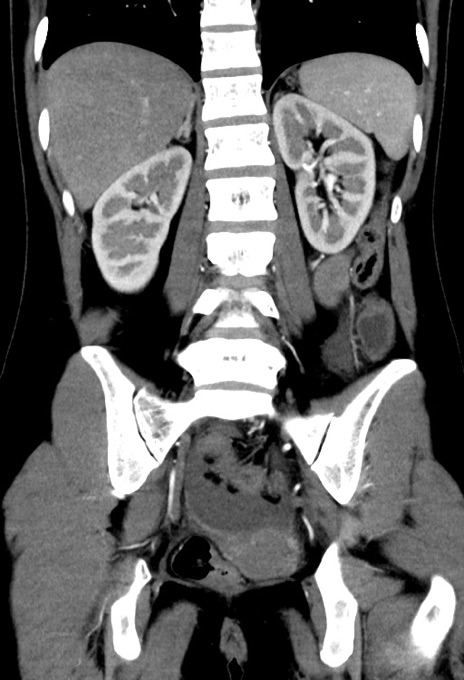

横断像

【症例】20歳代女性

【主訴】嘔吐、下腹部痛

【現病歴】昨日夕食後に嘔吐し下腹部痛が出現。本日になっても嘔吐持続し改善しないため来院。

【身体所見】意識清明、BT 37.2℃、BP 108/67mmHg、腹部:平坦、やや硬、下腹部正中から右にかけて圧痛あり、反跳痛軽度あり、tapping pain(+)。

【データ】WBC 13600、CRP 14.94